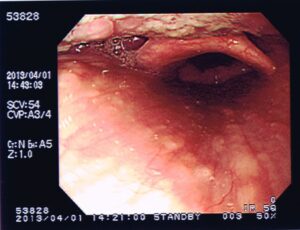

← 秋葉の声帯

左が閉じた状態、右が開いた状態